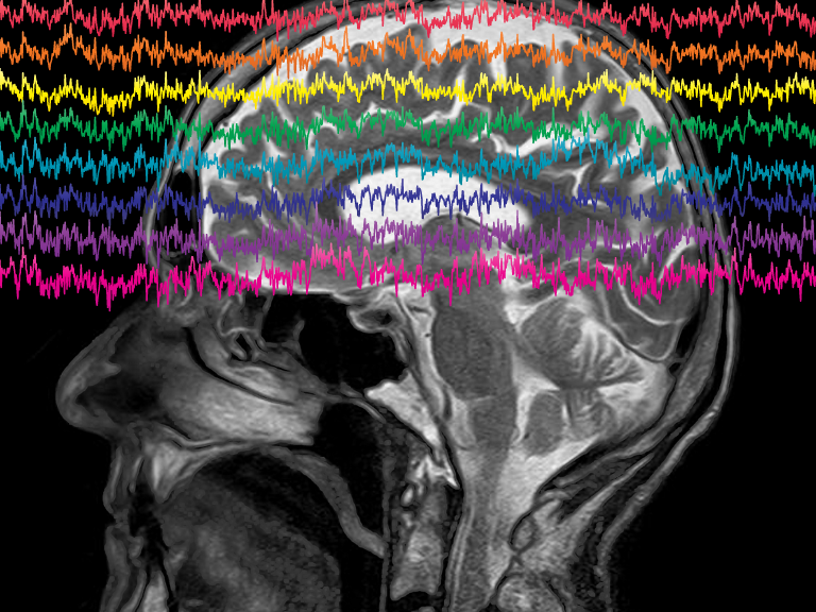

В последние годы создание интерфейсов «мозг — компьютер» позволило парализованным людям управлять роботизированными протезами. Команда под руководством нейрохирурга Эдварда Чанга (Edward Chang) из Калифорнийского университета в Сан-Франциско использовала этот принцип для создания «речевого нейропротеза» — устройства, которое декодирует мозговые волны, контролирующие движения мышц губ, челюсти, языка и гортани, формирующих каждый звук речи.

Пациент-доброволец, который вызвался протестировать устройство, пятнадцать лет назад перенес инсульт ствола головного мозга, вызвавший обширный паралич и лишивший его возможности говорить. Исследователи имплантировали электроды на поверхность мозга человека, над областью, контролирующей речь. Компьютер проанализировал нейронную активность, возникающую в мозге при намерении пациента произнести те или иные слова, в конечном итоге научившись различать 50 слов, из которых можно было составить более 1000 предложений. Например, на вопрос «Хотите пить?» компьютер позволяет мужчине ответить «Нет, я не хочу пить». По словам ведущего автора статьи Дэвида Мозеса (David Moses), слово появляется на экране через три-четыре секунды после того, как пациент пытается его произнести. Это не так быстро, как при обычной речи, но быстрее, чем другие доступные парализованным людям способы коммуникации.